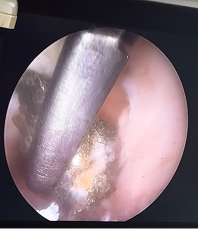

Рис. 4. Этап удаления осколка. Вид в ране; захват конхотомом; вид раны после удаления осколка; удаленный осколок в браншах конхотома.